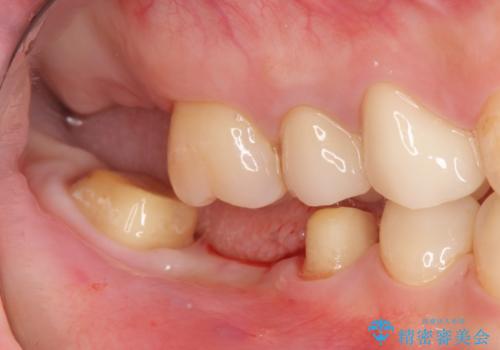

- 上下1本づつの歯を失い、噛めないことの改善を求めて来院されました。

保存可能な歯の虫歯・根管治療を行い、喪失した部分はインプラントを埋入、オールセラミックジルコニアクラウンを製作し審美的に仕上げていきます。

- 120万円(仮歯×6・ファイバーコア×2・ジルコニアクラウン×6・インプラント×2・チタンカスタムアバットメント×2)費用は治療当時の料金となります

今回下顎の欠損部位はブリッジも検討されましたが、並行性の観点から最後方臼歯の神経を取るリスクを抑えるためインプラント治療を選択しました。